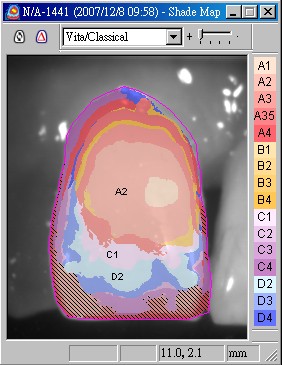

由於是前牙,本院採用Cynovad數位比色機比色(圖十六,並以高階數位單眼相機記錄牙齒的表面紋路及局部色澤(染色、斑點等)(圖十七),因此技師即使未親臨現埸,仍可得到最精準的比色資料。

圖十六 |